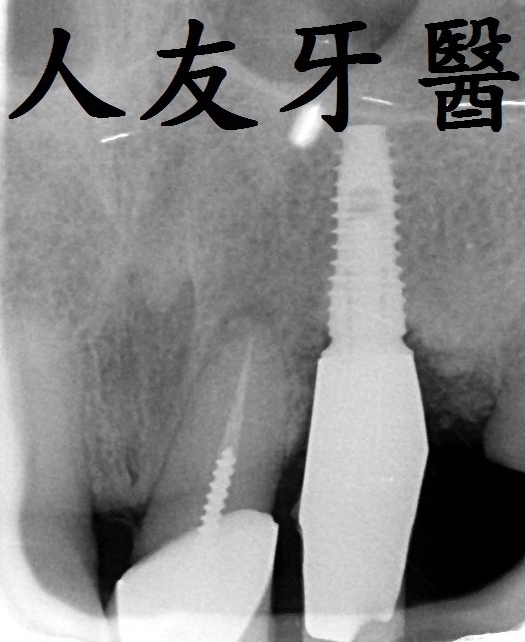

植牙常見問題 Q & A ?!